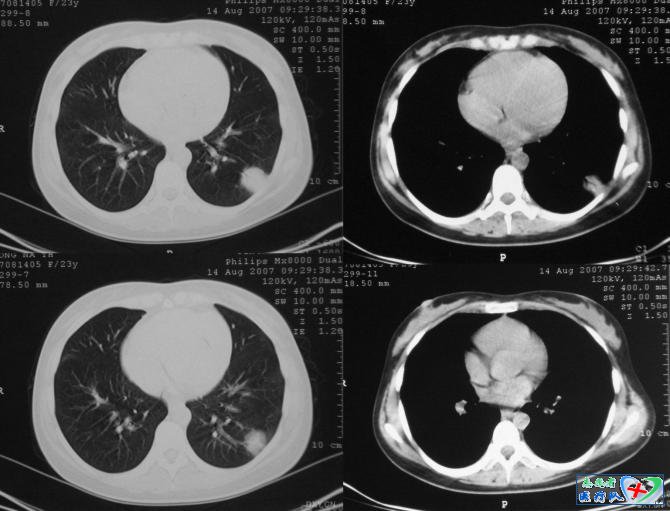

4、方形征

病变临近胸膜或叶间胸膜时,两侧缘可垂直于胸膜,呈刀切样,致病变呈方形。肺部炎症时,炎性渗出物沿肺泡孔向上下、左右、前后均匀扩散,形成各经线均匀相近的炎性病灶,但是当炎性渗出物扩散受胸膜或小叶间隔阻挡时,病变扩散受阻。方形征是球形肺炎的特征性表现,其CT表现有:

(1)病灶多位于肺野背侧,靠近胸膜;

(2)病灶多呈方形、楔形、三角形、圆形等表现,病灶临近胸膜侧常表现为典型的方形;

(3)病变中央密度高,周边密度较淡,表现为“晕征”;

(4)病变边缘可不规则,有锯齿状改变但较模糊;

(5)周围胸膜或叶间胸膜反映明显,广泛增厚,位于胸膜面下的病变接触面宽,呈广基相连,部分病例于病灶与胸壁之间可见一低密度线影。

(6)病变周围血管纹增粗、增多、扭曲,但无僵直和受牵拉;

(7)少数病灶内可见支气管充气征;

(8)抗炎治疗后病变明显缩小。